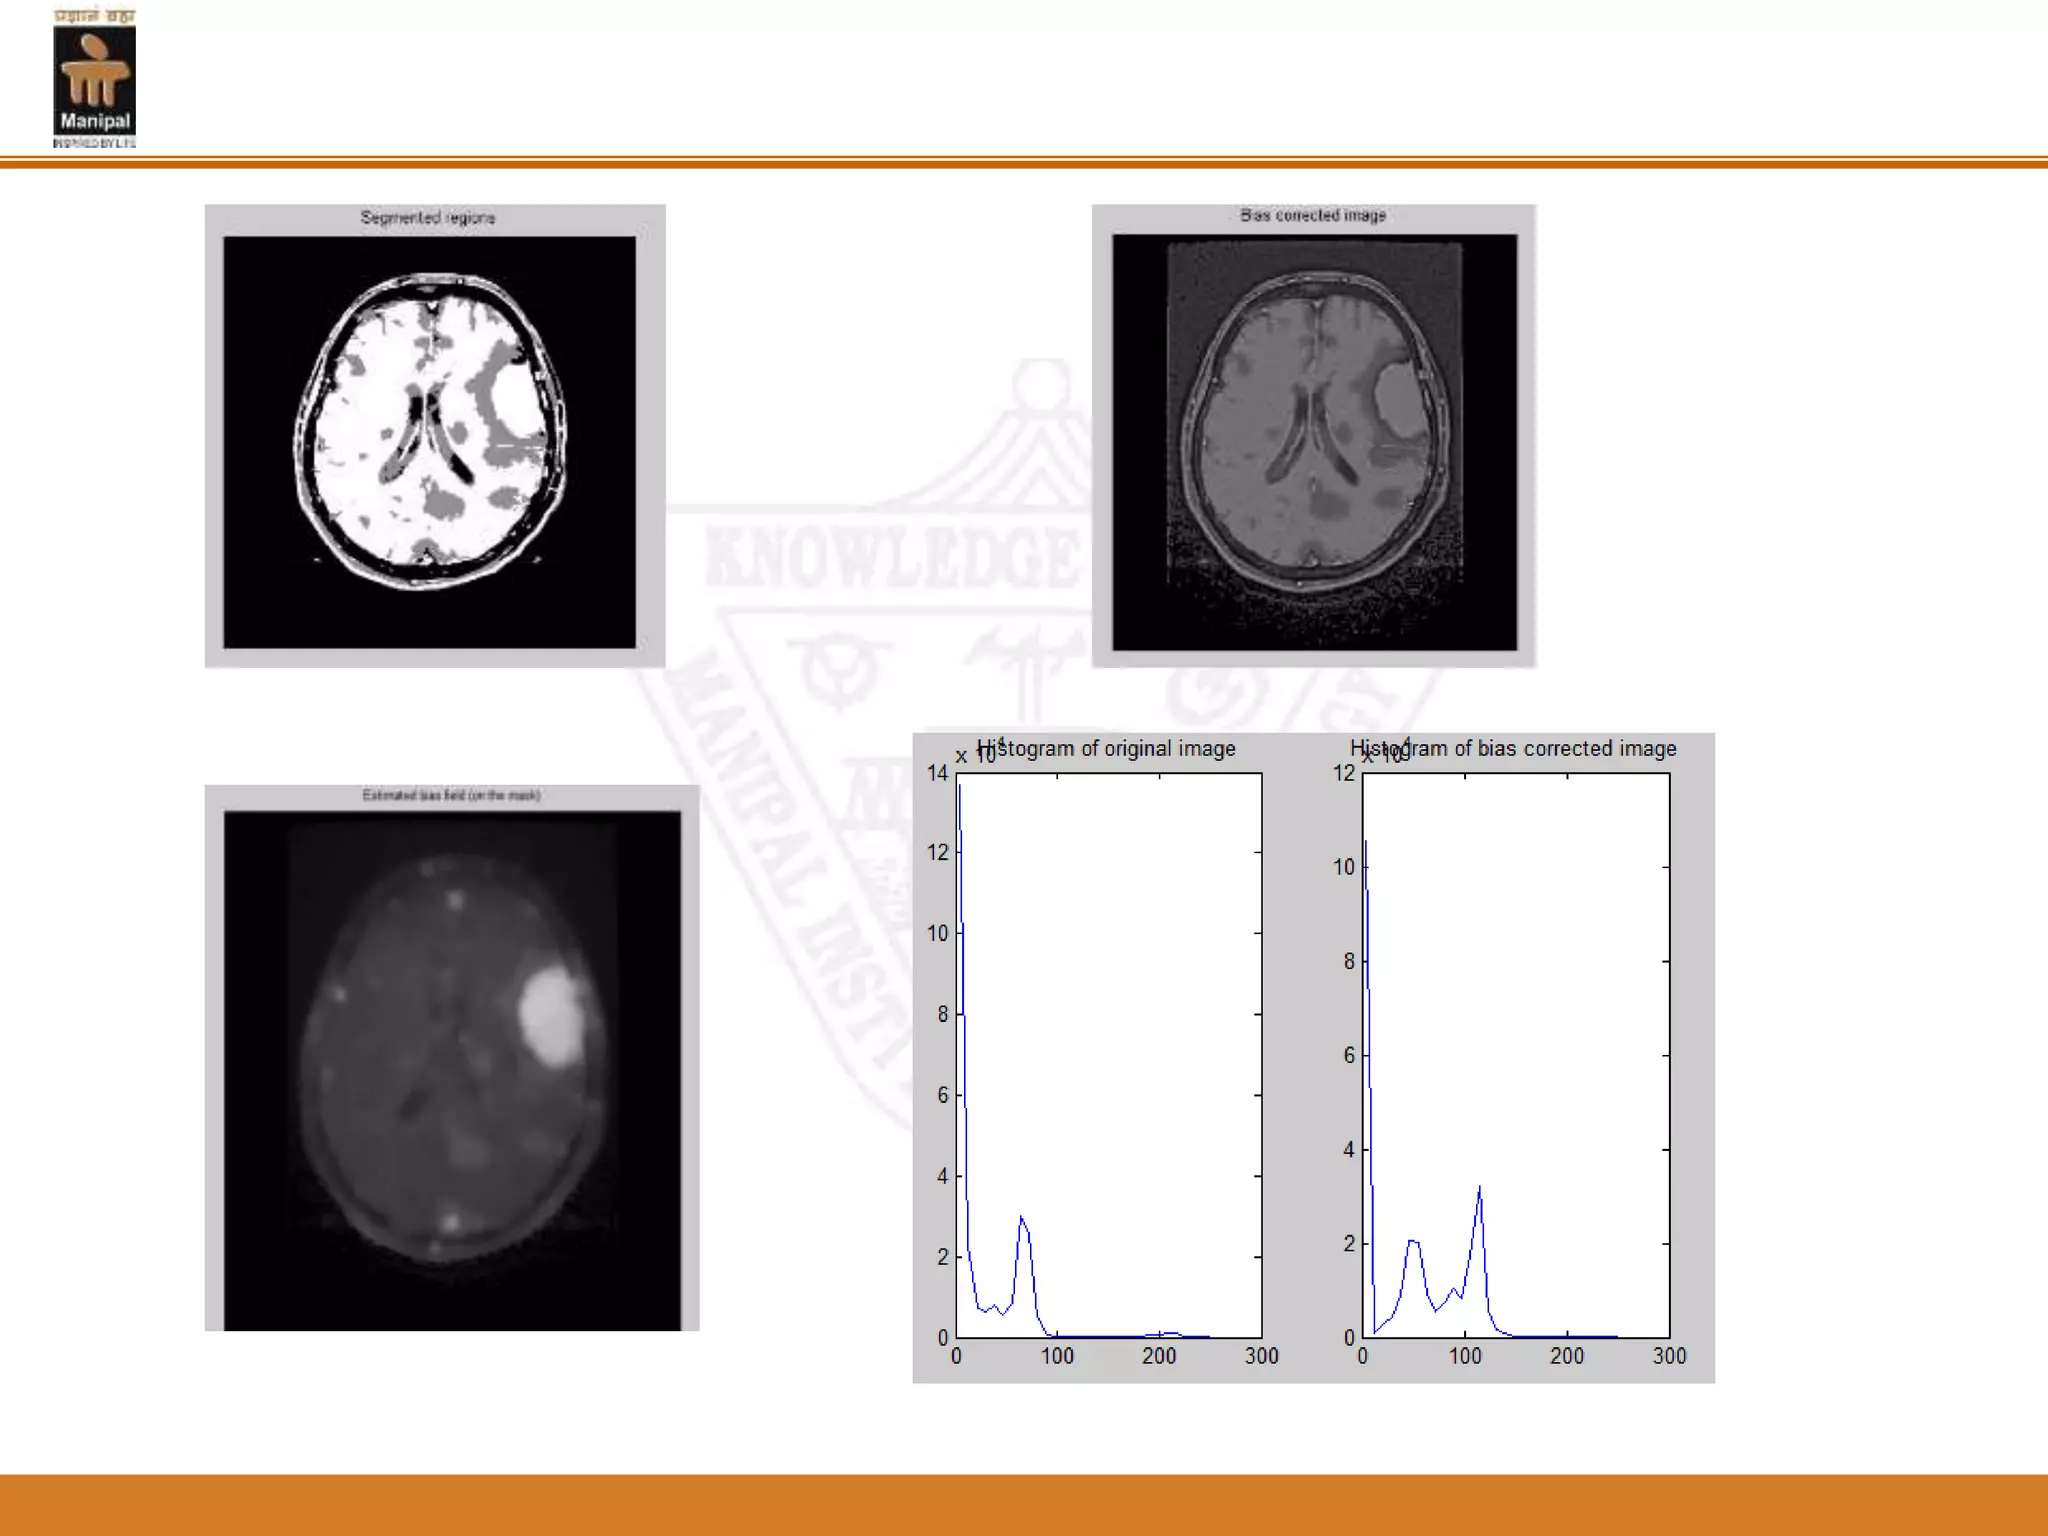

Multi-Phase level set evolution and Bias field correction

1) Set them value, the number of clusters c and the size Of the spatial constraint window used to average the Membership matrix. 2) Estimate an initial bias field signal B0 from the corrupted MRI images. 3) Calculate the membership matrix U_ik. 4) For each pixel take the average of the membership Matrix x around a window of specified value. Normalize the membership matrix so for each image pixel the summation of the membership values corresponding to different clusters equals to one. C start Multi-Phase level set evolution and Bias field correction

5) Calculate theprototype centres vi and estimate the bias Field Bk. C 6) Test if the difference between the norm of the previous calculated membership matrix and the norm of the current membership matrix ||Ul||− ||Ul+1|| is less than a pre-specified error or if the algorithm exceeds certain number of iterations than exit. stop

Result analysis Figure1: FuzzyC-means clustering (FCM) applied to the MRI

Figure 2: Alevel set segmentation